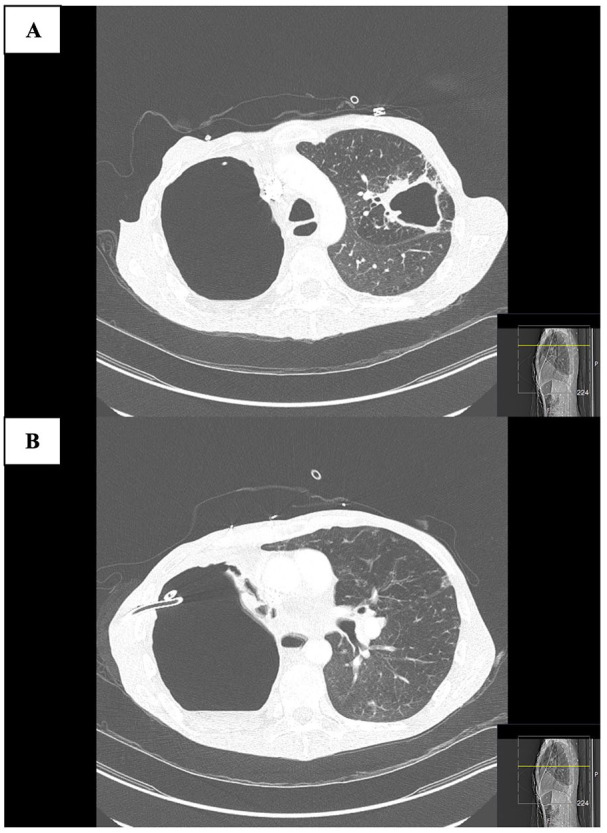

球孢子菌病是美国西南部的一种地方性疾病,可导致严重的肺部并发症,尤其是肺储备不良的慢性阻塞性肺疾病(COPD)患者。脓肿分枝杆菌易造成肺部结构性损伤,通常引起难以治疗的支气管扩张和空洞病变。我们报告一例58岁晚期慢性阻塞性肺病患者,30年前诊断为肺球虫菌病,入院前4年发现有脓疡分枝杆菌空洞性肺病的痰液和影像学证据,但未能随访。目前的表现是由于未经治疗的脓肿分枝杆菌感染的进展和潜伏的球虫感染的再激活。尽管开始进行抗真菌和抗生素治疗,但随后的过程因支气管胸膜瘘的发展和呼吸衰竭的恶化而复杂化,导致不利的结果。该病例强调了慢性阻塞性肺病患者并发感染的重叠临床和放射学特征以及破坏性结局相关的诊断挑战。及时的诊断检测和长期的综合治疗对于管理这种复杂的感染至关重要。

Coccidioidomycosis, endemic in the southwestern United States, can lead to severe pulmonary complications, particularly in chronic obstructive pulmonary disease (COPD) patients with poor lung reserves. Mycobacterium abscessus has a predisposition for structurally damaged lungs, commonly causing difficult-to-treat bronchiectasis and cavitary lesions. We present the case of a 58-year-old patient with advanced COPD and a remote history of pulmonary coccidioidomycosis diagnosed 30 years earlier, who was found to have sputum and radiographic evidence of M. abscessus cavitary lung disease 4 years prior to admission, but was lost to follow-up. The current presentation is attributed to the progression of untreated M. abscessus infection and reactivation of latent Coccidioides infection. Despite the initiation of antifungal and antibiotic therapy, the subsequent course was complicated by the development of bronchopleural fistula and worsening respiratory failure, leading to an unfavorable outcome. This case highlights the diagnostic challenges associated with overlapping clinical and radiologic features of concurrent infections and devastating outcomes in patients with COPD. Prompt diagnostic testing and prolonged comprehensive therapy are of paramount importance in managing such complex infections.